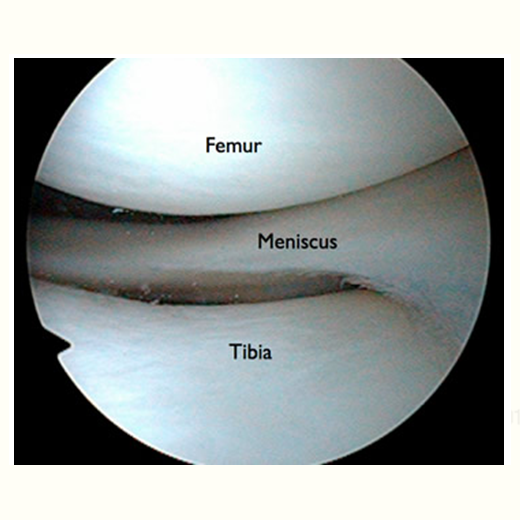

The meniscus is a rubbery, C-shaped cartilage in between the femur (thighbone) and tibia (shinbone). There are two menisci in each knee joint, the inner medial meniscus and the outer lateral meniscus. The outer edges are fairly thick while the inner surfaces are thin. The meniscus provides smooth knee motion, stability and contributes to a healthy knee through its shock absorber effect. During the various phases of the walking cycle, forces shift from one meniscus to the other, and forces on the knee can increase to 2 – 4 times body weight. While running, these forces on the knee increase up to 6 – 8 times body weight. There are even higher forces when landing from a jump.